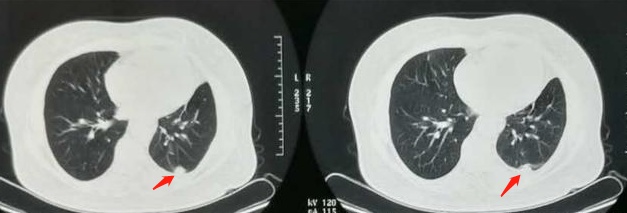

下图这位62岁的老爷子,发现时肿瘤已经侵犯了胸膜,但手术切除配合术后化疗,今年是第3年复查,没有复发转移征象:

这位老爷子是幸运的,但癌症的可怕之处就在于早期症状不明显,出现症状时常常就已经失去手术机会。